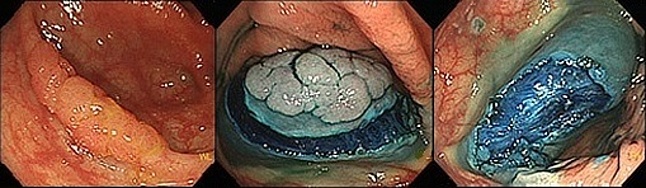

大腸がんが粘膜内にとどまっている表在型の場合には内視鏡的切除にて治療することができます。治療は粘膜下層に生理食塩水などの液体をを注入して腫瘍を浮かせた後に、輪っかのような器具(スネア)をかけて切除します。がんが早期で発見された場合、腫瘍は隆起しておらず扁平(平たい)なものが多いです。当院ではこのような腫瘍も確実に切除するために、スネアに加えて鉗子も使用し、腫瘍を引っ張りながら切除を行っています。